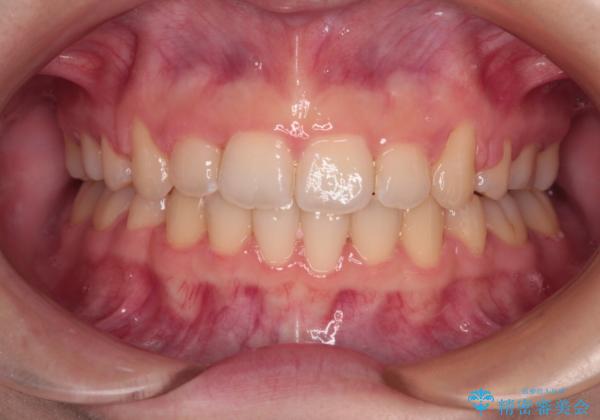

舌の突出癖があり、前歯の移動量も多くなるため、治療期間は長くなると予想されましたが、13ヶ月という予定の半分程度の期間で終えることができました。

※写真にある上顎装置はメタルブラケットではありません。メーカー在庫都合などにより別の装置を使用しております。